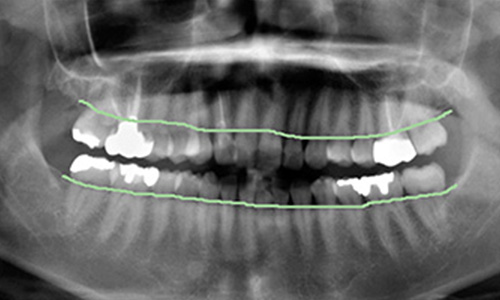

レントゲン写真では、はっきりとわかる歯槽骨の吸収は認められませんが、歯槽骨の硬い骨を表す白線が消えています。歯槽骨の頂点に線を引いていますが、ほぼ平行で一直線状を呈しています。